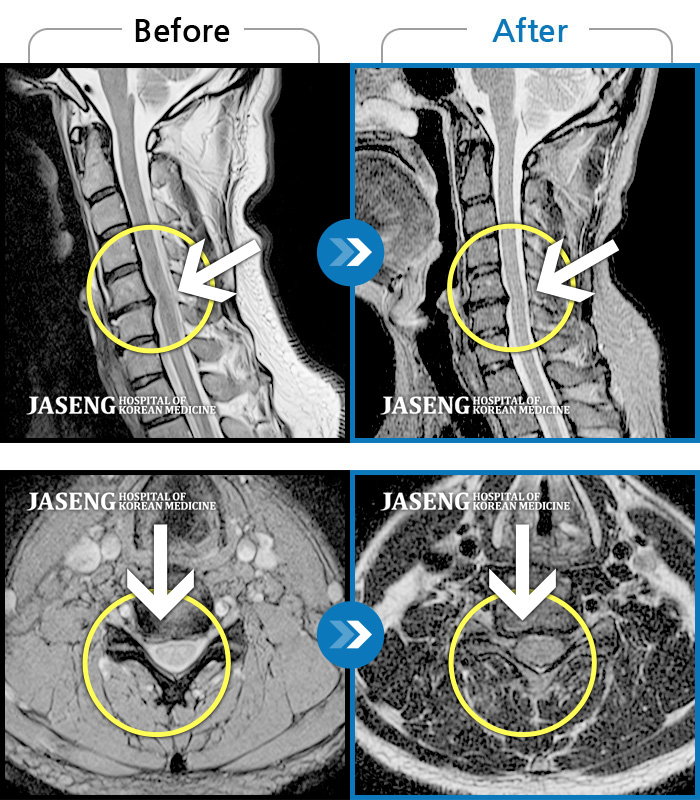

목디스크

인천 · 강아현 원장

처음 내원시 목에서 등으로 이어지는 통증 및 우측 팔 저림 증상이 심했고, 약간의 근력저하도 동반되어 일상생활이 어려운 상태였습니다.

촬영시기

2024.04.06 ~ 2024.11.16

2024.11.22

조회수 17,045